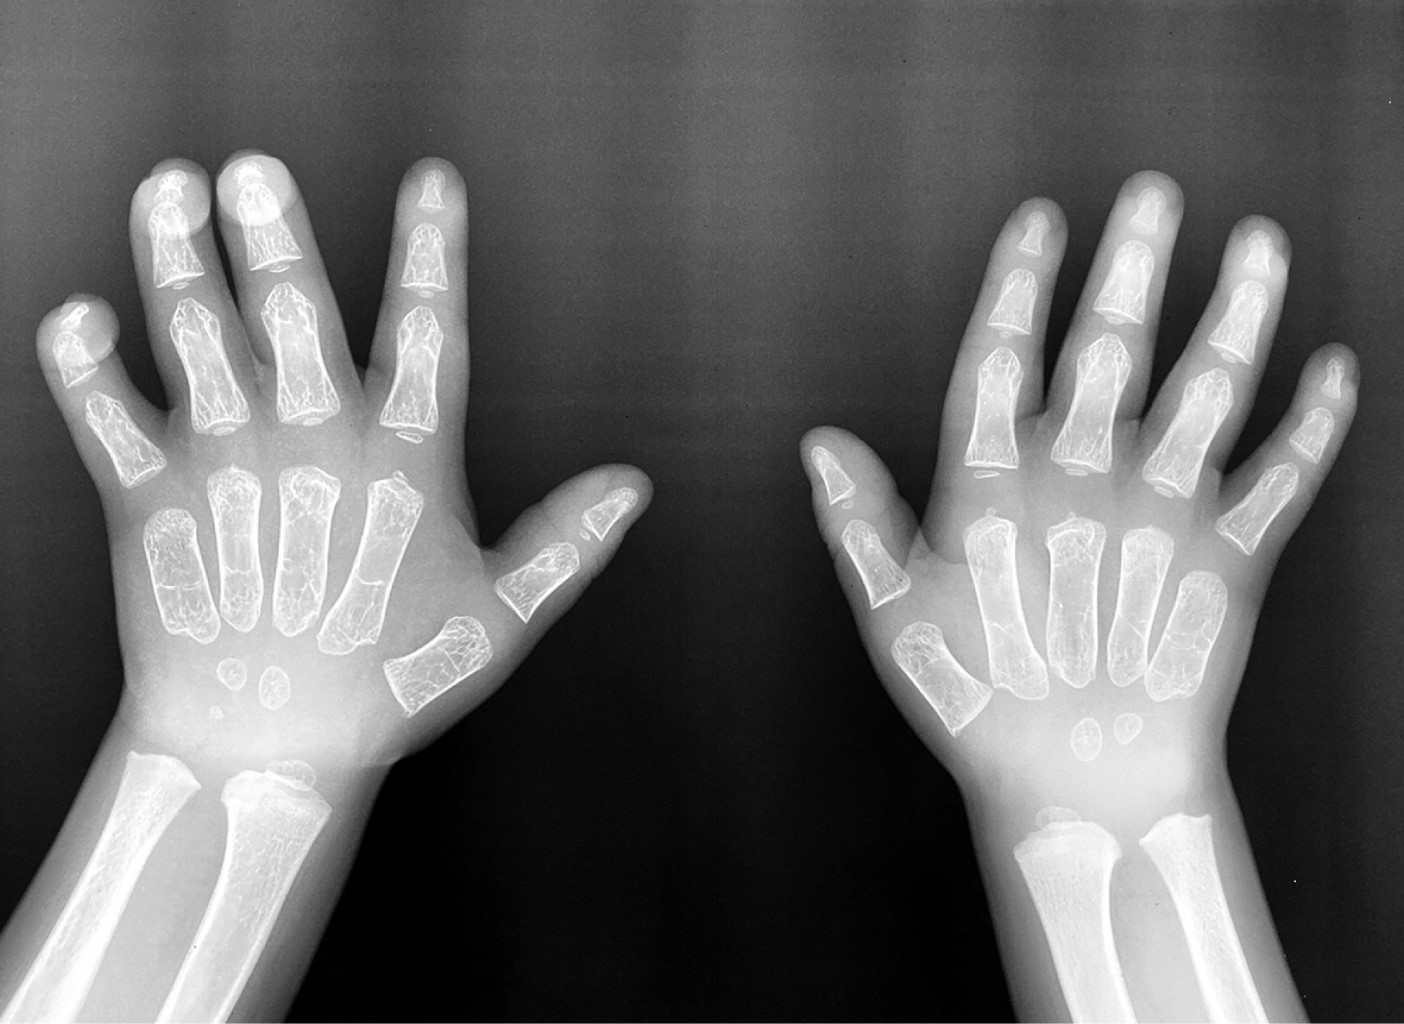

Evolution of a patient with type II mucopolysaccharidosis who started treatment with idursulfase at three years of age

Introduction: Mucopolysaccharidosis type II (MPS II) or Hunter syndrome is a lysosomal disease caused by deficiency of the enzyme iduronate-2-sulfatase, responsible for the degradation of glycosaminoglycans. Case presentation: Male patient diagnosed with MPS II at three years of age. The clinical picture included coarse facial features, splenomegaly, limited joint mobility, recurrent airway infections, and psychomotor retardation. Treatment with idursulfase was started and, after 24 months, his growth and joint mobility have improved; in addition, the volume of the spleen decreased, and he has not presented respiratory infections, but the neurological disorders persist. Conclusions: Currently, the availability of idursulfase, as enzyme replacement therapy, has improved the prognosis of MPS II patients.

Figure 1

Figure 2

Figure 3

Figure 4

Figure 5